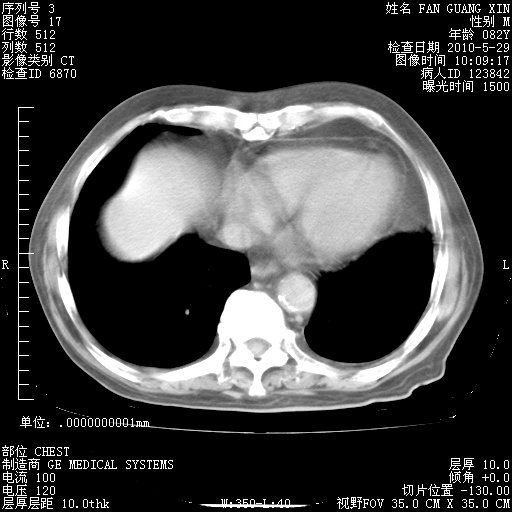

再治疗10天后的肺部CT

再治疗10天后的肺部CT 纵膈窗